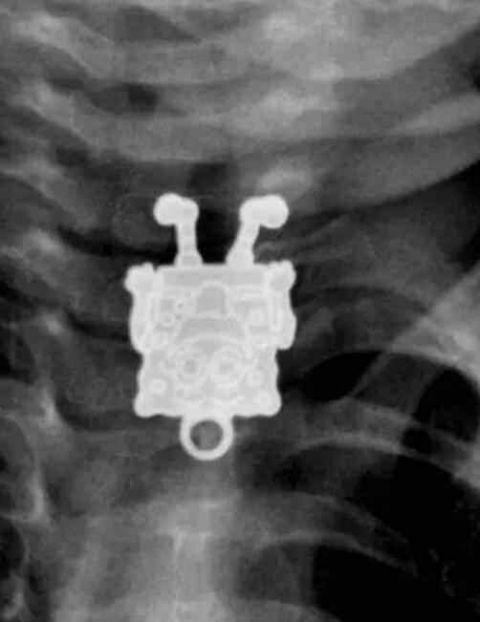

海绵宝宝?